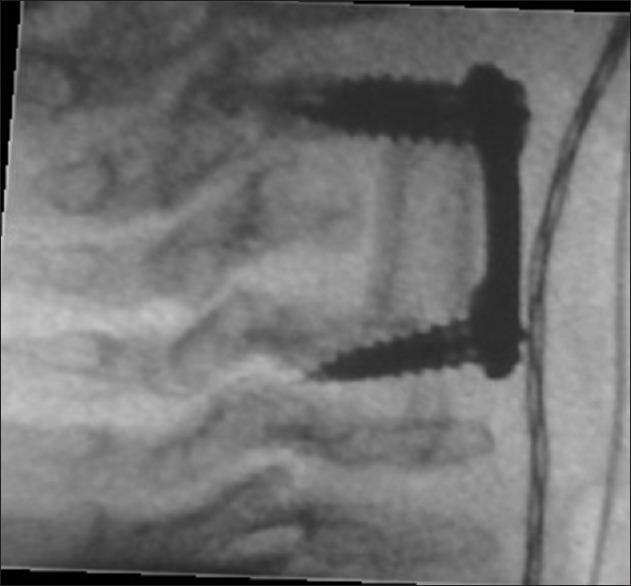

Morquio's syndrome is associated with systemic skeletal hypoplasia leading to generalized skeletal deformation. The hypoplasia of odontoid process is frequent association, which is responsible for atlantoaxial dislocation causing compressive myelopathy. However, development of sub-axial cervical kyphotic deformity unassociated with odontoid hypoplasia is extremely rare, and coexistence of dorsal kyphotic deformity is not reported in the western literature till date and represents first case. Current case is 16-year-old boy, who presented with severe kyphotic deformity of cervical spine with spastic quadriparesis. Interestingly, he also had additional asymptomatic kyphotic deformity of dorsal spine; however, odontoid proves hypoplasia was not observed. He was only symptomatic for cervical compression, accordingly surgery was planned. The patient was planned for correction of cervical kyphotic deformity under general anesthesia, underwent fourth cervical corpectomy with resection of posterior longitudinal ligament and fusion with autologous bone graft derived from right fibula, which was refashioned approximating to the width of the corpectomy size after harvesting and fixed between C3 and C5 vertebral bodies and further secured with anterior cervical plating. He tolerated surgical procedure well with improvement in power with significant reduction in spasticity. Postoperative X-ray, cervical spine revealed complete correction of kyphotic deformity cervical spine. At follow-up 6 months following surgery, he is doing well. Successful surgical correction of symptomatic cervical kyphotic deformity can be achieved utilizing anterior cervical corpectomy, autologous fibular bone graft, and anterior cervical plating.

黏多糖贮积症Ⅳ型与全身性骨骼发育不全相关,可导致全身骨骼变形。齿状突发育不全是常见的伴发情况,可导致寰枢椎脱位,引起压迫性脊髓病。然而,颈椎下颈椎后凸畸形的发生与齿状突发育不全无关,极为罕见,西方文献至今未报道过伴有胸椎后凸畸形的病例,本病例为首例。本例患者为一名16岁男孩,表现为颈椎严重后凸畸形伴痉挛性四肢瘫。有趣的是,他还伴有胸椎无症状性后凸畸形;然而,未观察到齿状突发育不全。他仅表现为颈椎受压症状,因此计划进行手术。患者计划在全身麻醉下矫正颈椎后凸畸形,接受了第四颈椎椎体次全切除术,切除后纵韧带,并采用取自右腓骨的自体骨移植进行融合,腓骨在获取后重新塑形,使其宽度接近椎体次全切除的尺寸,固定于C3和C5椎体之间,并进一步用颈椎前路钢板固定。他对手术耐受良好,肌力有所改善,痉挛明显减轻。术后颈椎X线显示颈椎后凸畸形完全矫正。术后6个月随访时,他恢复良好。利用颈椎前路椎体次全切除术、自体腓骨移植和颈椎前路钢板固定,可成功地对有症状的颈椎后凸畸形进行手术矫正。